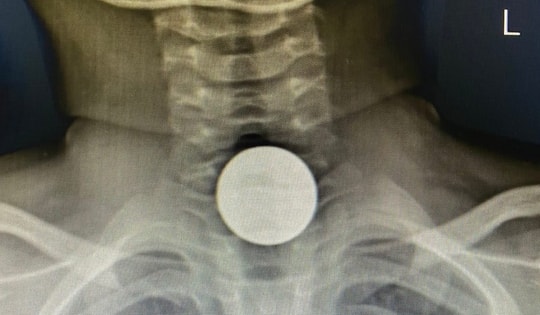

Nuốt pin cúc áo, bé 2 tuổi bỏng nặng thực quản